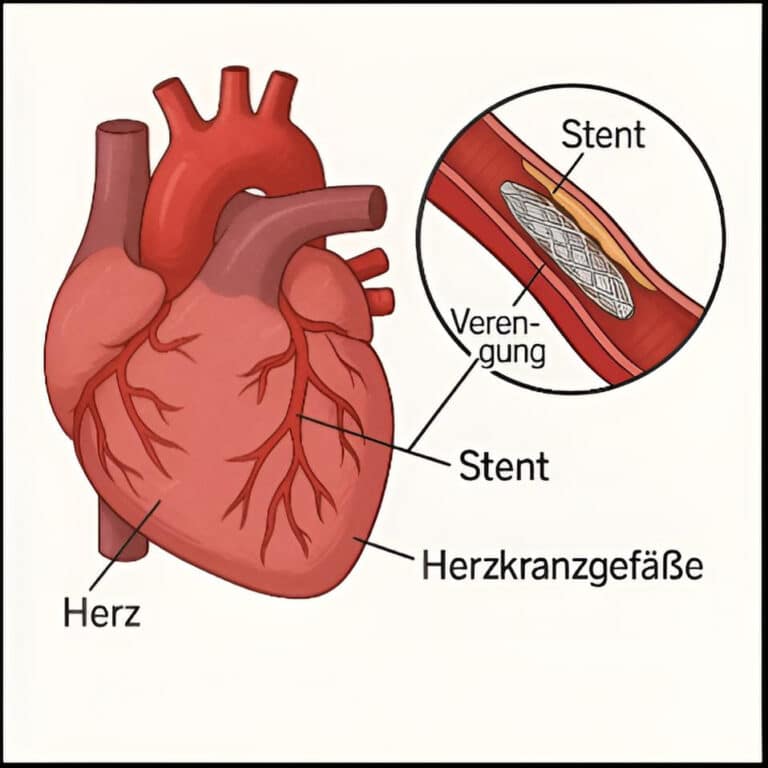

Warum gesunde Herzkranzgefäße so entscheidend sind

Unser Herz schlägt rund 100.000-mal pro Tag. Dafür benötigt es eine konstante Versorgung mit Sauerstoff und Nährstoffen. Diese Aufgabe übernehmen die Herzkranzgefäße (Koronararterien). Sie entspringen direkt aus der Hauptschlagader (Aorta) und umspannen das Herz muskulär wie ein Netz. Kommt es zu Verengungen, sogenannten Engstellen (Stenosen), kann der Herzmuskel nicht mehr ausreichend versorgt werden. Hieraus resultierende Folgen reichen von Brustschmerzen bis zum Herzinfarkt.

Was ist ein Herz-Stent?

Ein Herz-Stent ist ein kleines, gitterartiges Röhrchen aus Metall oder bioresorbierbarem Material, das in eine verengte Koronararterie eingesetzt wird. Ziel: Die Engstelle dauerhaft offenhalten, damit das Blut ungehindert fließen kann. Das kann:

- die Sauerstoffversorgung des Herzens verbessern und dadurch

- bei akutem Herzinfarkt das Leben retten

- akute Beschwerden lindern (z.B. Angina pectoris)

Wichtig: Bei stabiler Koronarer Herzkrankheit (KHK) dient der Stent primär der Symptomkontrolle und nicht der Prognoseverbesserung.